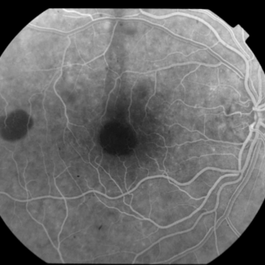

This 68 year old man was referred with a maculopathy but with normal visual acuity. He is thought to have multifocal Best Disease; there is no evidence of inflammation or uveitis and no history of cancer. Macular exam reveals yellow subretinal pigment clumping in each macula, including the foveal area. OCT shows moderate hyper-reflective PED, with no evidence of subretinal fluid or macular edema. Angiography reveals blocking defects due to pigment clumping with no evidence of CNVM.

Multifocal Best Disease Multifocal Best DiseaseJan 31 2015 by Thomas A. Ciulla, MD, MBA, FASRS Angiography reveals blocking defects due to pigment clumping with no evidence of CNVM. Photographer: Charlotte Harris Condition/keywords: adult vitelliform dystrophy, Best disease